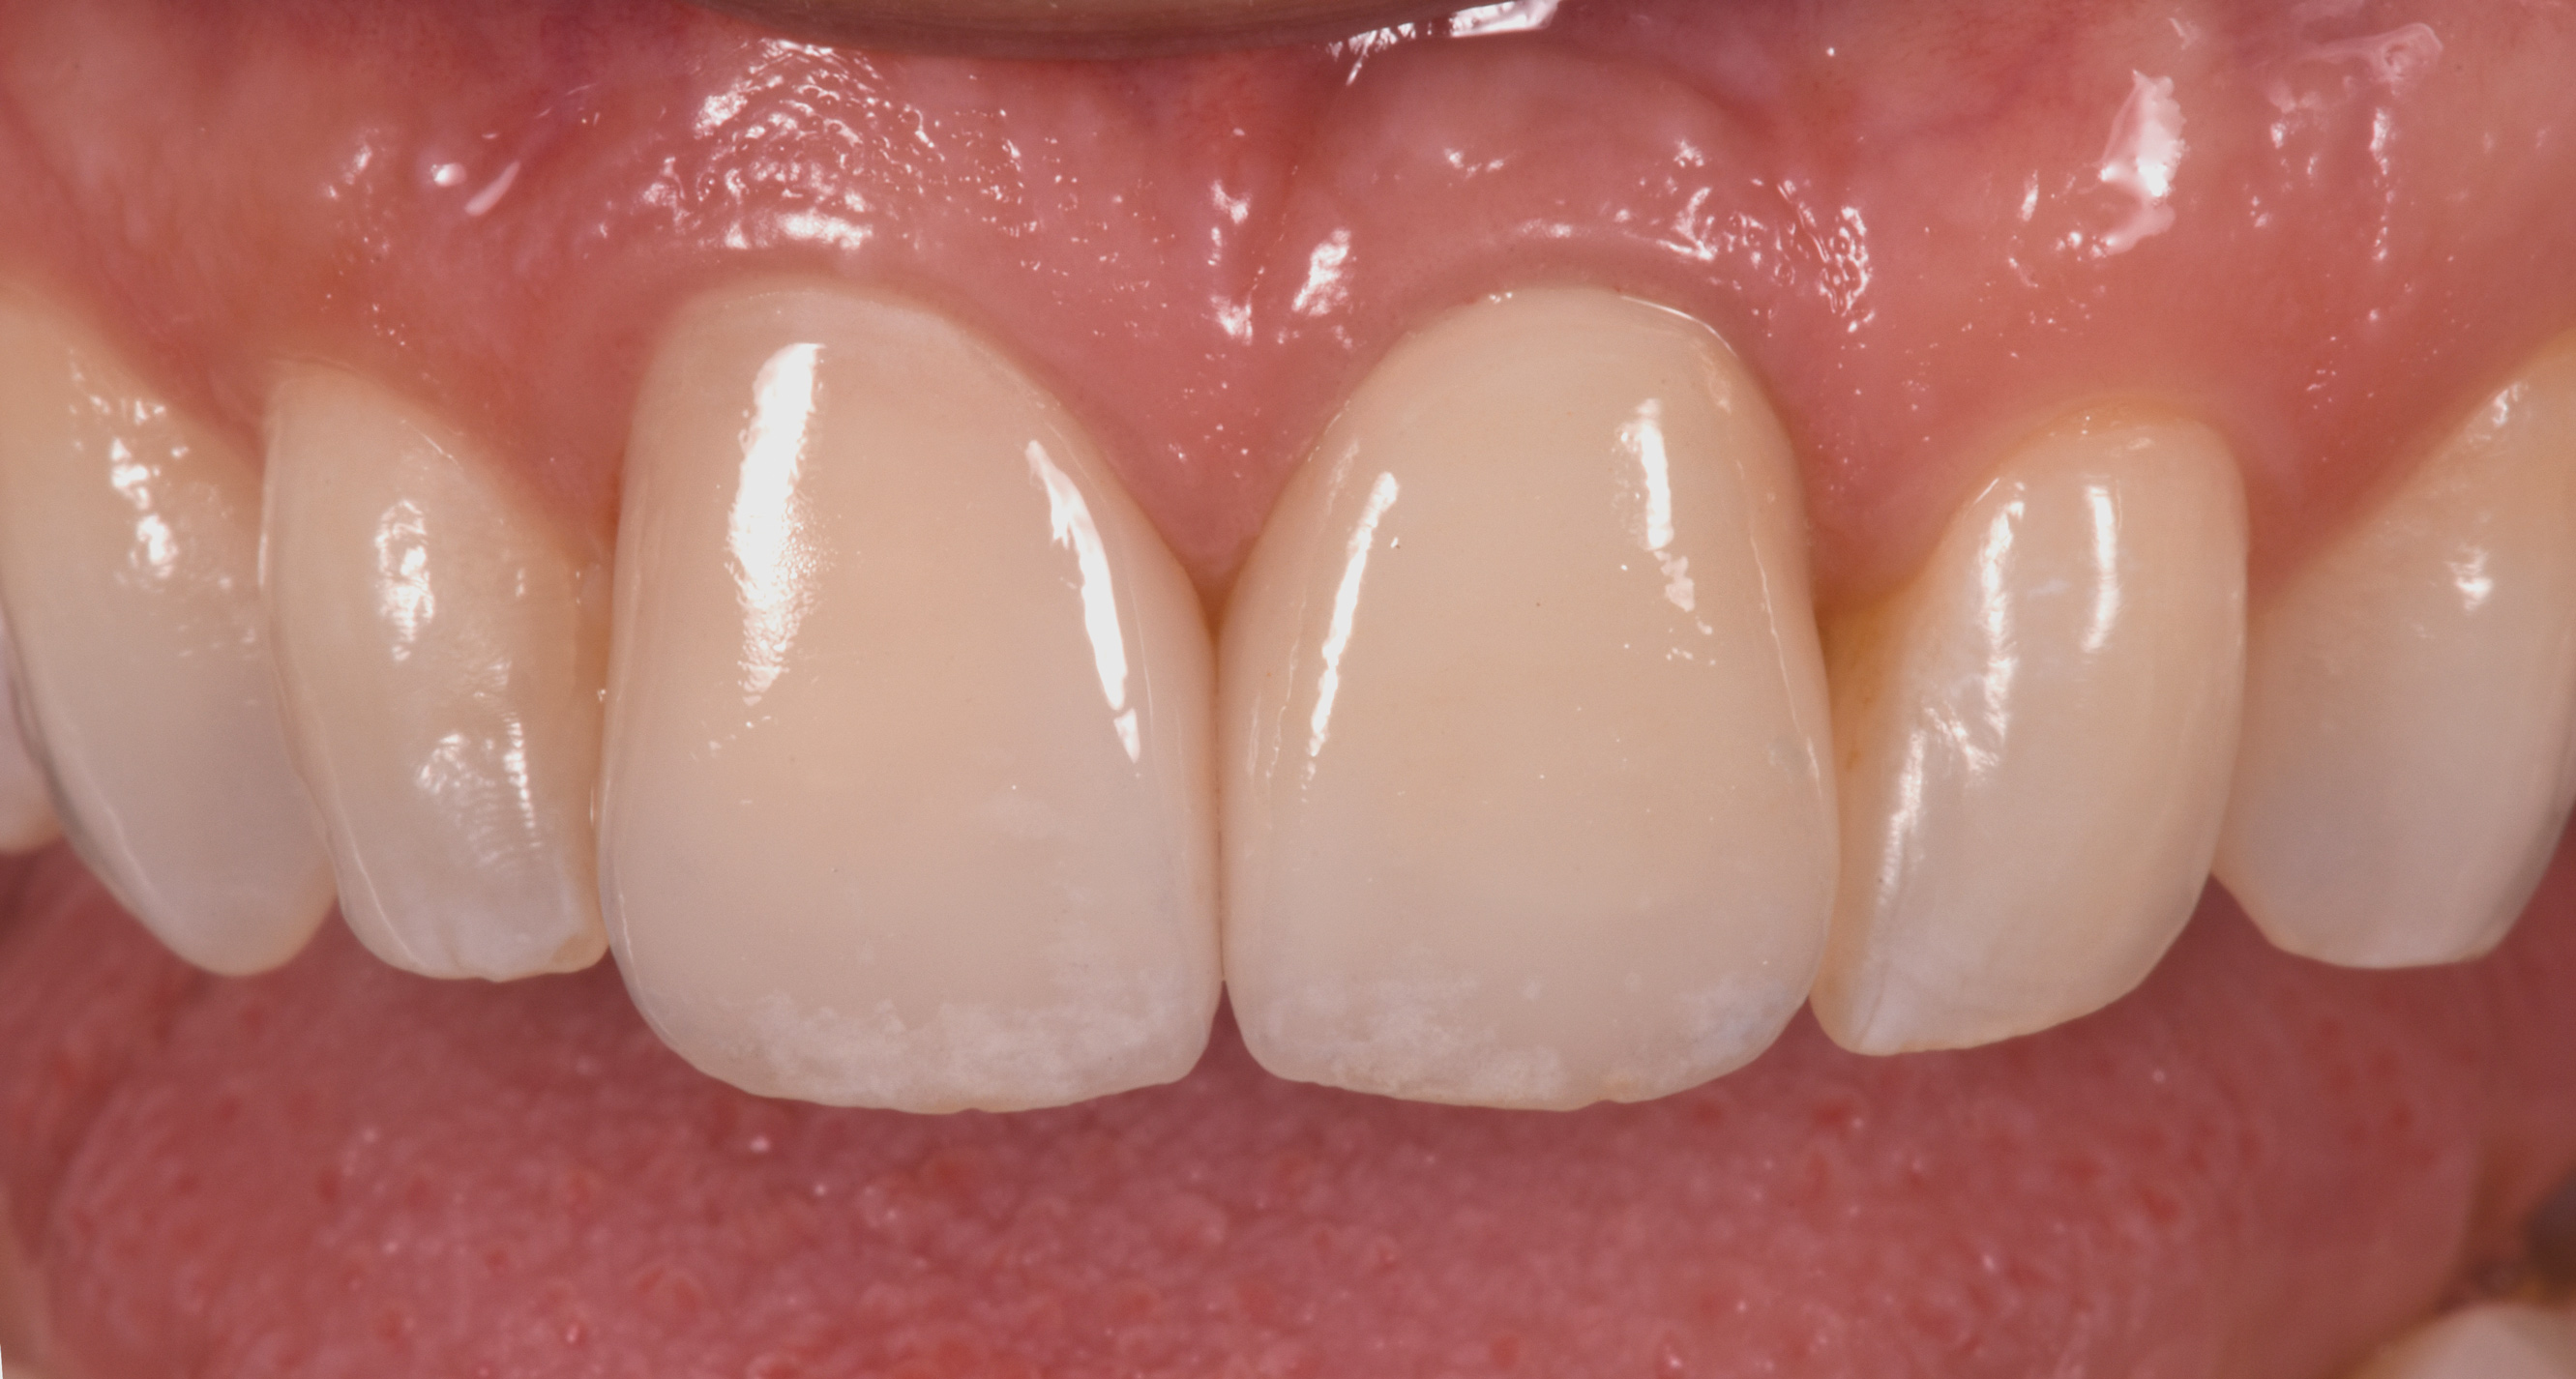

Fig 10. Labial view (laboratory [Fig 10] and clinical [Fig 11]) of crown Nos. 8 and 9 (implant-retained crown using angulated screw channel).

Figure 10

Fig 10 and Fig 11. Labial view (laboratory [Fig 10] and clinical [Fig 11]) of crown Nos. 8 and 9 (implant-retained crown using angulated screw channel).

Figure 11

Fig 12. Incisal view (clinical) of crown Nos. 8 and 9.

Figure 12